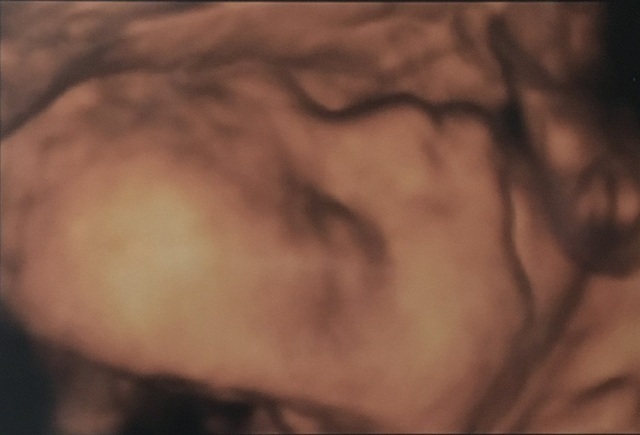

28週2日(28w2d・男の子)|みゆ* さん

エコー写真撮影時のエピソード:

なかなか検診で顔を見せてくれず、ママとパパは困っていたけどこの日は4D検診だったからかとてもお利口さんでたーくさん顔を見せてくれた。悪阻も少しずつなくなり、落ち着いて過ごせた。赤ちゃんの体重も徐々に増えていき、産まれてくるのがとても楽しみでした。